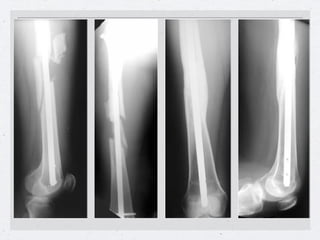

Clavo centromedular de tibia

Curvatura adaptada

Clavo hueco

Clavo de tibia

bloqueo proximal      bloqueo distal

Clavo centromedular detibia • Tabla ortopédica • Tracción longitudinal • Tracción trans- calcánea o estribo • Rodilla flexionada Instalación para • Control radioscópico enclavado tibial. de la reducción

Instalación para enclavadode tibia • El canal endomedular se aborda por delante de la espina tibial • Introducción de la guía, del alisador y finalmente el clavo.

Clavo Centromedular deTibia Curvatura adaptada Clavo hueco

Enclavado de tibiaen fractura cerrada Clavo sin Bloqueo Clavo con Bloqueo con aletas Clavo con Bloqueo con Pernos

Callo óseo luegodel enclavado centromedular de tibia a foco cerrado. Ventajas del Clavo Centro medular a foco Cerrado •Preservación del Hematoma •No desperiostización •Callo óseo Luminoso

Clavo de tibia bloqueoproximal bloqueo distal